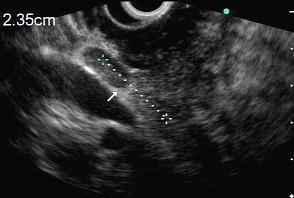

问题 男性,50岁,上腹隐痛,食欲不振3个月。1个月来出现黄疸且进行性加深,体重明显减轻,查体全身明显黄染,肝未触及,深吸气时可触到肿大胆囊底部,无触痛。化验血胆红素15mg/dl,尿检胆红素阳性图中胰腺病变可能的诊断是 ( )

选项 A、胰腺囊腺癌 B、胰腺癌 C、胰腺囊肿 D、慢性胰腺炎 E、正常

答案 B